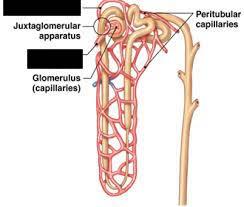

Afferent/efferent arteriole

Collecting duct

Descending/Ascending loop (of nephron)

Distal (convoluted) tubule

Glomerular capsule (=Bowman's capsule)

Glomerulus (=glomerular capillaries)

Juxtaglomerular apparatus

Nephron

Peritubular capillaries

Proximal (convoluted) tubule

Renal artery/vein

Renal corpuscle